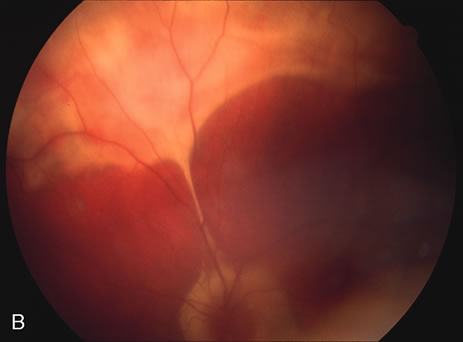

DIFFUSE SUBRETINAL FIBROSIS

Some patients present with subretinal bands that extend between chorioretinal scars. In addition there may be initial active yellow choroidal lesions that subsequently become atrophic. Vitreous cells are usually present although they may be few and difficult to detect. Visual acuity loss in these cases may be due to active choroidal neovascularization, subretinal bands under the fovea, or from cystoid macular edema. The vast majority of affected patients are women with a mean age of 27 years and both eyes are usually involved. The affected individuals tend to be myopic.49 The age range is from 6 years to 76 years and there is no racial predilection.40 Whether it is a separate disease or a more severe form of multifocal choroiditis is controversial (Figs. 10 and 11). Aggressive therapy is warranted because it has a poorer prognosis than most cases of multifocal choroiditis. This syndrome has been called either diffuse subretinal fibrosis or progressive subretinal fibrosis syndrome.

Fig. 10. A. Fundus photograph showing the subretinal fibrosis extending from the disc to the periphery in a case of diffuse subretinal fibrosis. B. Fundus photograph showing the marked fibrosis in the midperiphery. C. Multifocal choroiditis type lesions noted in the inferior retina.

Fig. 11. A. Subretinal fibrosis in a case of multifocal choroiditis. B. Fellow eye showing classic coalescent hyperpigmented chorioretinal scars of multifocal choroiditis. These scars also can be seen in presumed histoplasmosis syndrome, but the subretinal fibrosis is extremely rare in presumed ocular histoplasmosis syndrome (POHS).